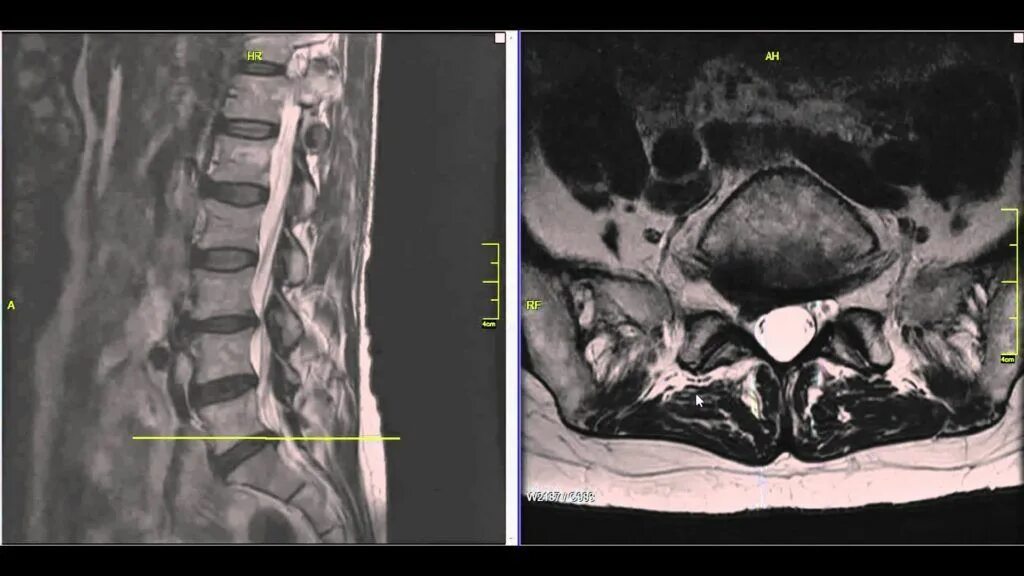

Грыжа диска мрт